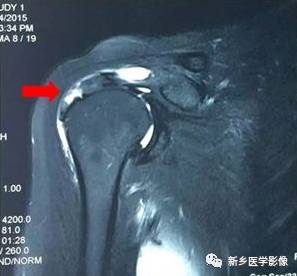

病例一:

红色箭头:冈上肌腱滑囊层撕裂